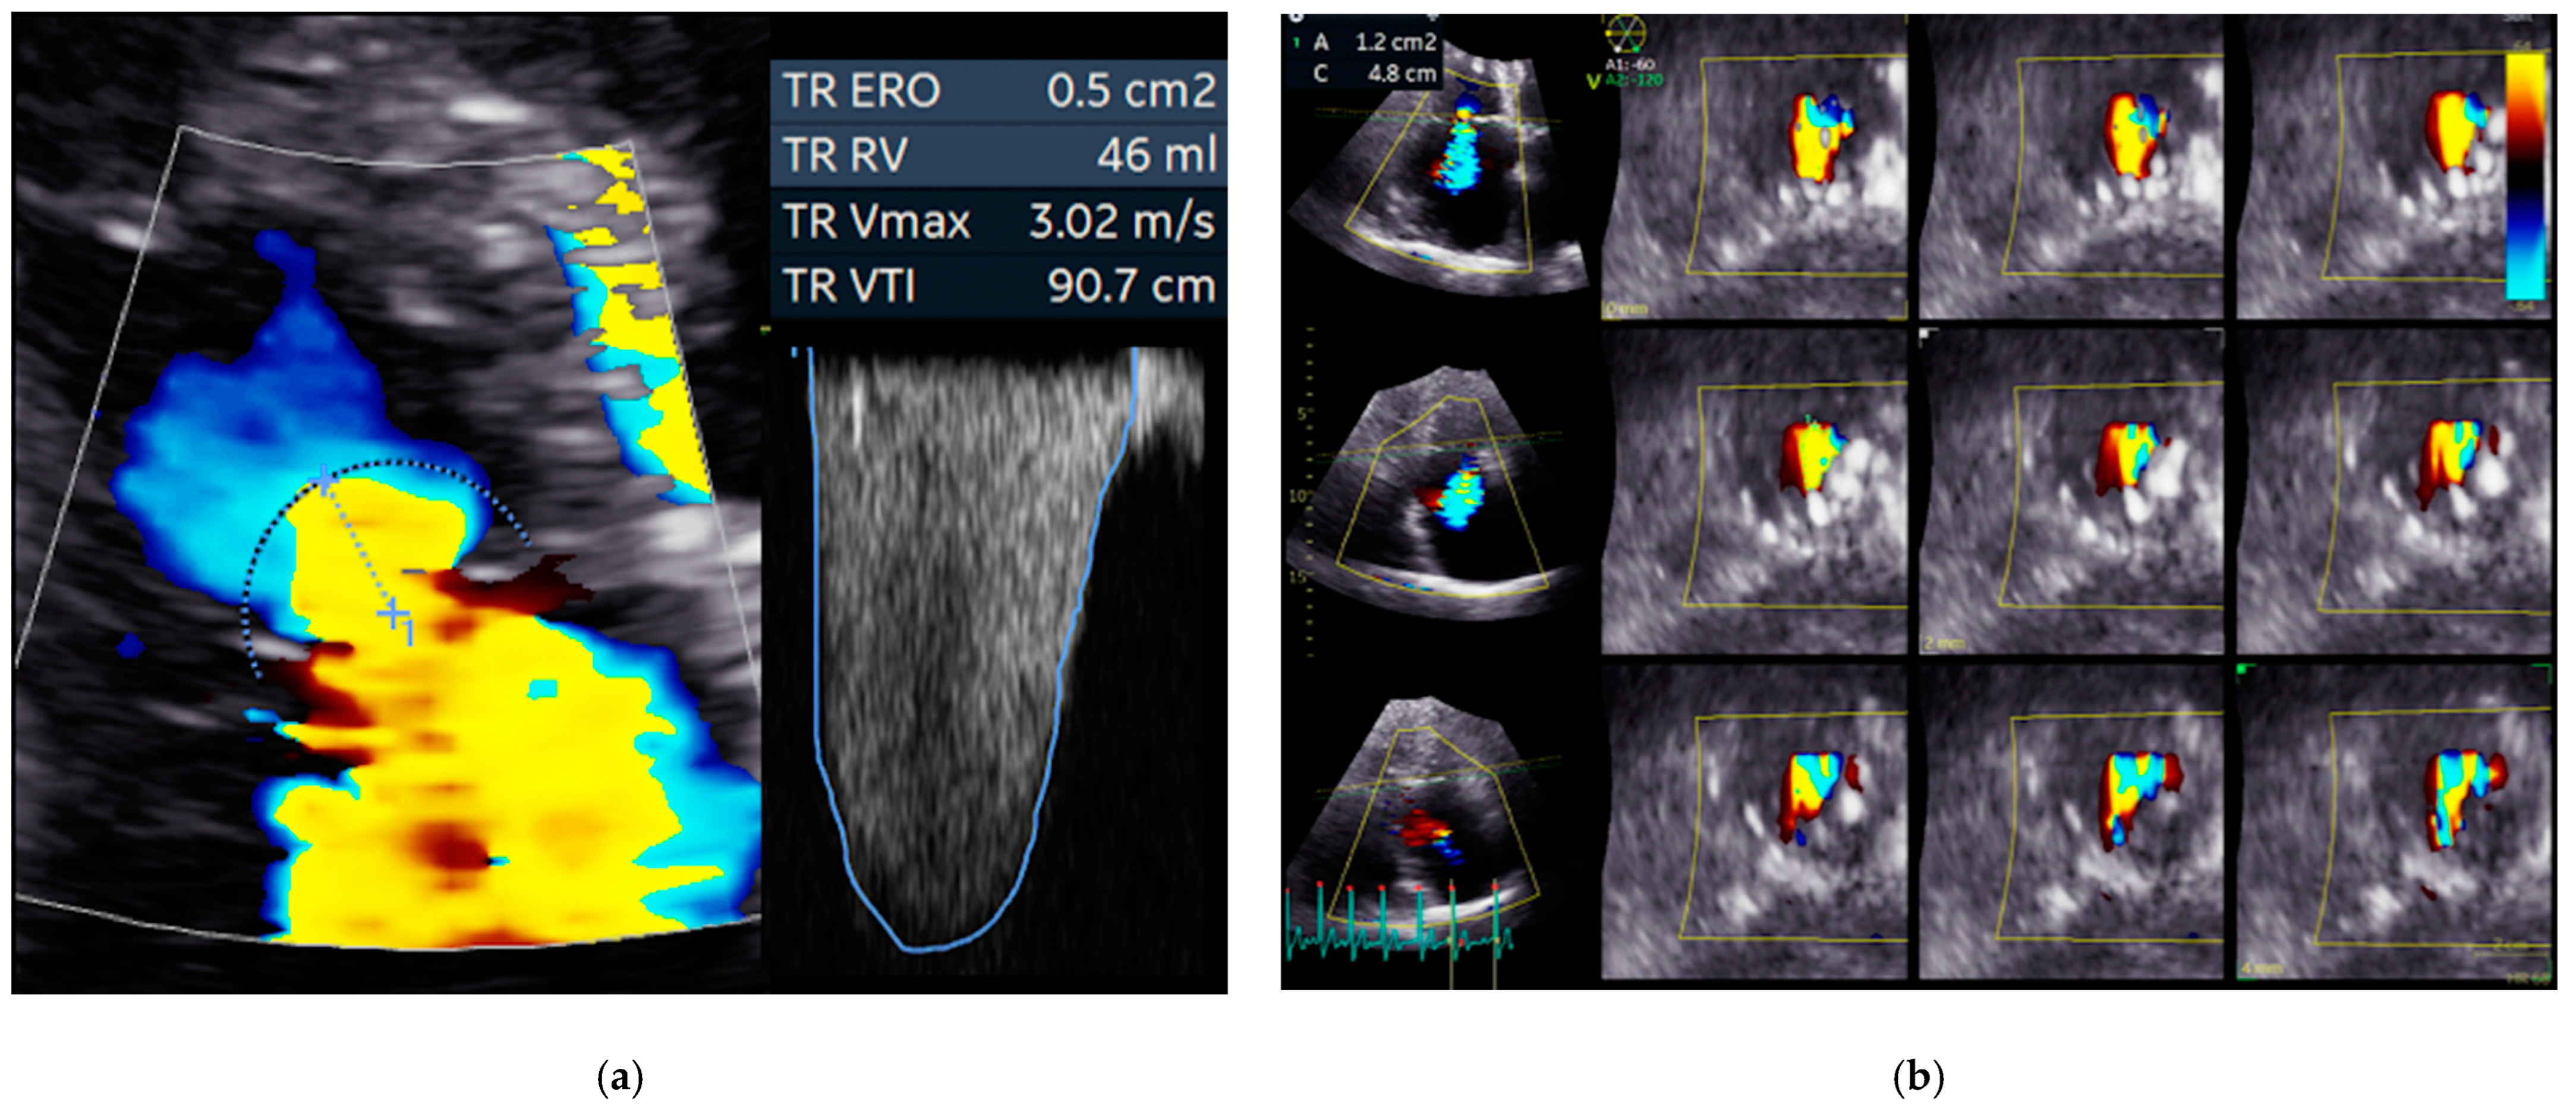

- Hahn, R.T. State-of-the-art review of echocardiographic imaging in the evaluation and treatment of functional tricuspid regurgitation. Circ. Cardiovasc. Imaging 2016, 9, 1–15. [Google Scholar] [CrossRef] [Green Version]

- Hahn, R.T.; Thomas, J.D.; Khalique, O.K.; Cavalcante, J.L.; Praz, F.; Zoghbi, W.A. Imaging Assessment of Tricuspid Regurgitation Severity. JACC Cardiovasc. Imaging 2019, 12, 469–490. [Google Scholar] [CrossRef] [PubMed]

- Abdellaziz, D.; Geraldine, O.; Nadira, H.; Eleonora, A.; Jing, Y.; Hahn, R.T. Quantifying Tricuspid Regurgitation Severity. JACC Cardiovasc. Imaging 2019, 12, 560–562. [Google Scholar] [CrossRef]

- Badano, L.P.; Hahn, R.; Zanella, H.; Araiza Garaygordobil, D.; Ochoa-Jimenez, R.C.; Muraru, D. Morphological Assessment of the Tricuspid Apparatus and Grading Regurgitation Severity in Patients With Functional Tricuspid Regurgitation: Thinking Outside the Box. JACC Cardiovasc. Imaging 2019, 12, 652–664. [Google Scholar] [CrossRef]